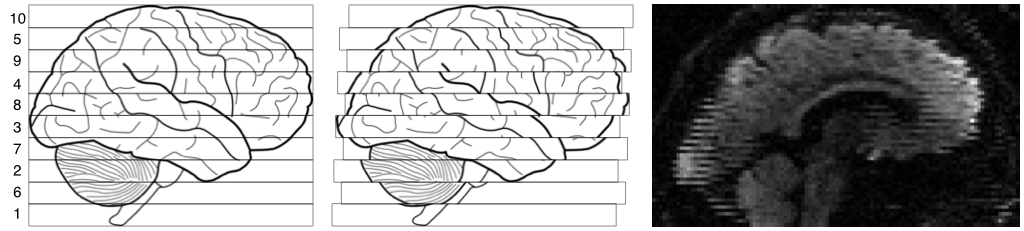

| Explanation of zig-zag pattern from intra-volume movement. |

|---|

|

| The leftmost image shows the outline of a brain, and ten "slices" acquired in the order indicated by the numbers on the left. The middle image shows the same brain, but now there was a continouos translation in the Post->Ant direction. The rightmost image shows an actual MR image displaying the same telltale pattern. |